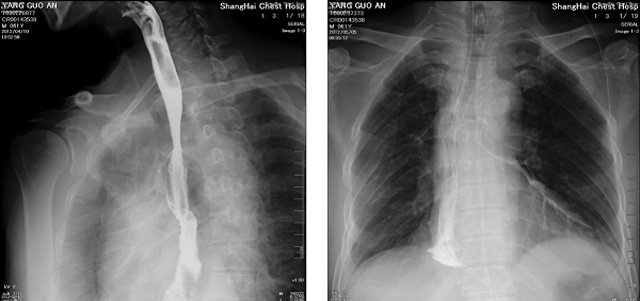

DR設(shè)備在2020年的新冠疫情中,加速了市場調(diào)整。以醫(yī)院為主的向二三級市場轉(zhuǎn)變。特別是小巧靈活的移動DR設(shè)計(jì),填補(bǔ)CT和磁共振不能三維檢查的缺點(diǎn),滿足內(nèi)科外科特別是骨科的影像診斷需求。還有懸吊DR設(shè)備CT斷層射線系統(tǒng)。使用錐束成像技術(shù)對整個(gè)脊柱和整個(gè)下肢進(jìn)行了體積三維掃描。無需使用對比劑,即可使用X射線呼吸功能標(biāo)測來模擬模擬氣流和血流,以評估患者的肺動脈血栓。